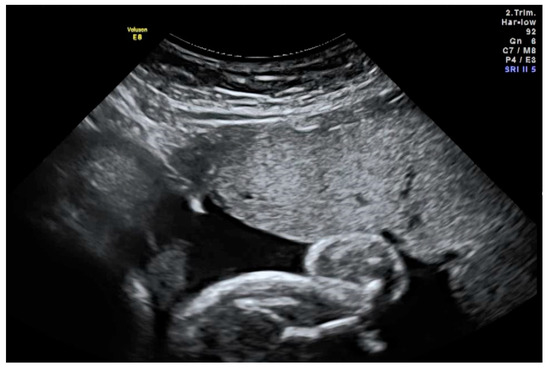

Study visits 2 to 4 (V2–V4) mark the treatment phase of the trial. Three intra-amniotic injections of ER004 (see Figure 1) are planned, approximately three weeks apart (with a minimum interval of two weeks between the injections):

Figure 1. Ultrasound-guided injection of the study drug into the amniotic cavity. Advancement of the needle must be continuously visualised. In this image, the needle tip (white) is located correctly in the amniotic fluid (black) underneath the placenta.